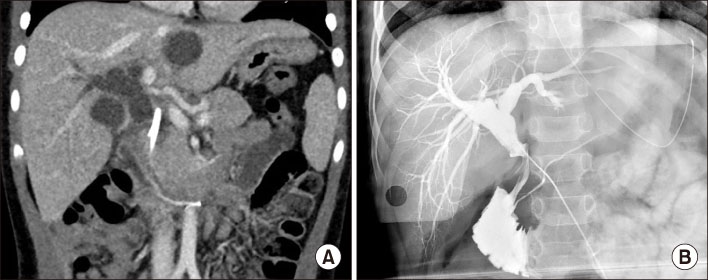

Contrast-enhanced abdominal CT scan. (A) CT scan taken two months before admission shows no visible bile duct dilatation or bile lake in the upper abdomen. (B) CT scan taken at the admission shows stenosis at proximal common bile duct with common hepatic duct dilatation and a bile lake at S2/3 of the liver.

Fig. 1 Contrast-enhanced abdominal CT scan. (A) CT scan taken two months before admission shows no visible bile duct dilatation or bile lake in the upper abdomen. (B) CT scan taken at the admission shows stenosis at proximal common bile duct with common hepatic duct dilatation and a bile lake at S2/3 of the liver.